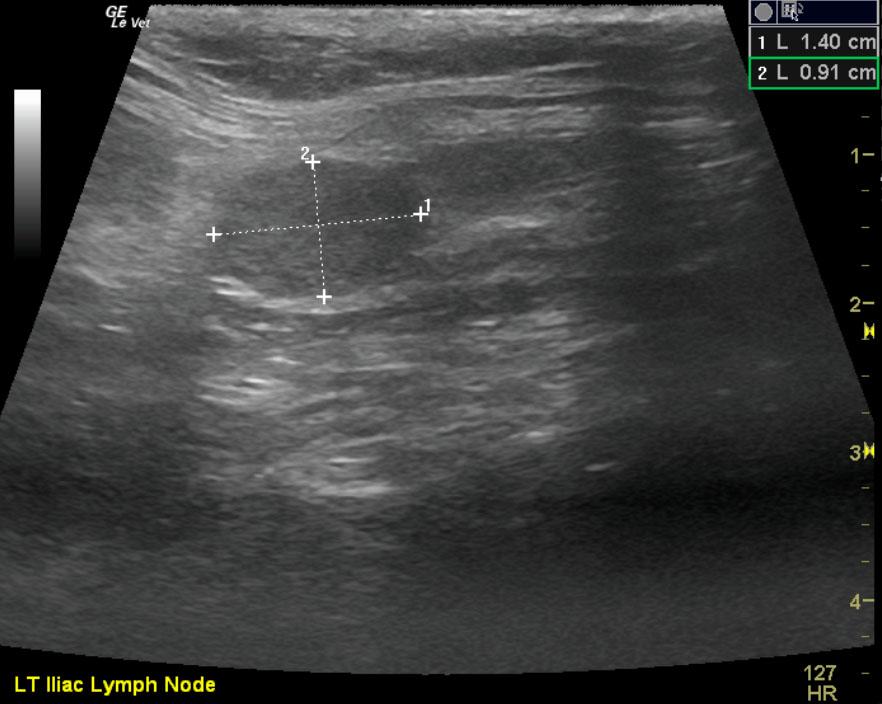

The patient is a feline DSH, MN, 8 year old. Concern for abdominal tumor due to decrease in appetite. Blood work is wnl. Urine specific gravity 1.045.